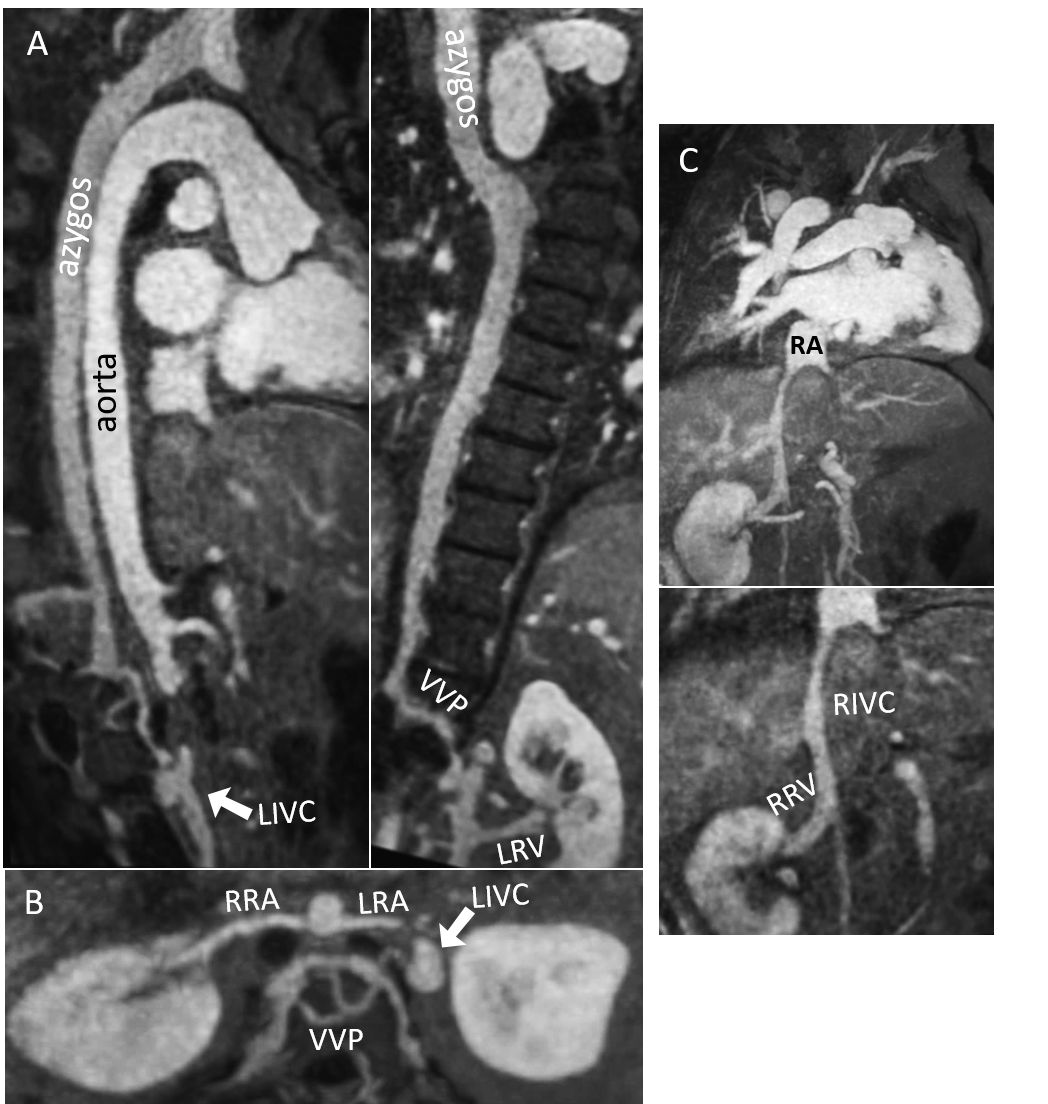

Interestingly, iNAV CE-MRA demonstrated dual inferior vena cava (IVC)- the left IVC was constituted from an azygos continuation into the vertebral venous plexus, and the right IVC had the anatomically correct connection with the right atrium. The right and left renal venous drainage was into right and left IVCs respectively (Fig 2). The pelvis and thigh station was beyond the MRA field of view. However, CTA additionally demonstrated paraumbilical venous collateralization between the superficial epigastric and hepatic portal veins (Fig 3). The iliofemoral venous system drained into the vertebral venous plexus and left IVC, while collateral tributaries from the lower extremity terminated into the paraumbilical vein and right IVC. Occlusive venous thrombosis of the external right iliac vein was identified and treated with staged thrombectomy and thrombolysis.

Fig 2- Demonstration of dual inferior venal cava anatomy using image-based navigator (iNAV) gadolinium enhanced MRA. (A) The azygos continuation joins the vertebral venous plexus (VVP), from which the left inferior vena cava (LIVC) originates. There is drainage of the left renal vein (LRV) into the LIVC. Inset- there is normal connection of the hemiazygos to the azygos vein. (B) Axial maximal intensity projection reformats demonstrate the relationship between the left renal artery (LRA), right renal artery (RRA), LIVC, and VVP. (C) The right renal vein (RRV) is a branch of the right inferior vena cava (RIVC), which terminates into the right atrium (RA). Notice continuation of the RIVC inferior to the origin of the RRV.

Fig 2- Demonstration of dual inferior venal cava anatomy using image-based navigator (iNAV) gadolinium enhanced MRA. (A) The azygos continuation joins the vertebral venous plexus (VVP), from which the left inferior vena cava (LIVC) originates. There is drainage of the left renal vein (LRV) into the LIVC. Inset- there is normal connection of the hemiazygos to the azygos vein. (B) Axial maximal intensity projection reformats demonstrate the relationship between the left renal artery (LRA), right renal artery (RRA), LIVC, and VVP. (C) The right renal vein (RRV) is a branch of the right inferior vena cava (RIVC), which terminates into the right atrium (RA). Notice continuation of the RIVC inferior to the origin of the RRV.  Fig 3- Twin curved multiplanar reformats from CTA imaging also demonstrated collateralization through the paraumbilical vein; proximal connection with the superficial epigastric vein (white arrow) and distal connection with the hepatic portal vein (black arrow).